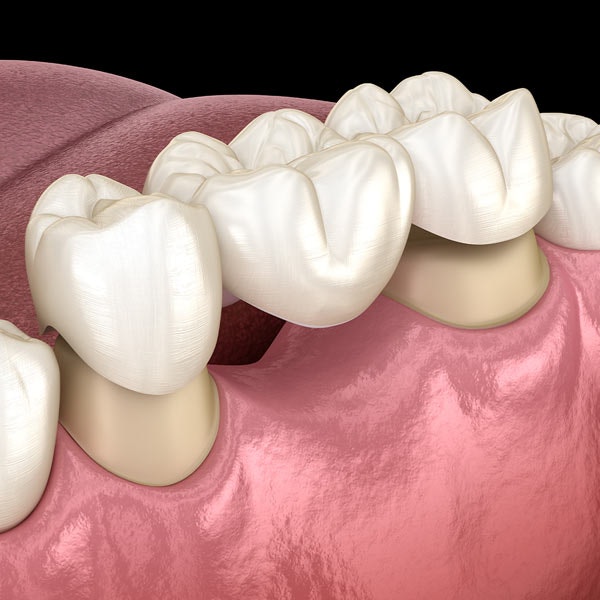

Dental Bridges

If you're missing one or more consecutive teeth, a dental bridge may be the restorative option for you. Dental bridges include one or more artificial teeth attached to the adjacent teeth with porcelain dental crowns. Dental bridges can correct problems with chewing and speaking while increasing your bite strength. In addition to traditional bridges, we can also use dental implants for unbeatably sturdy results.